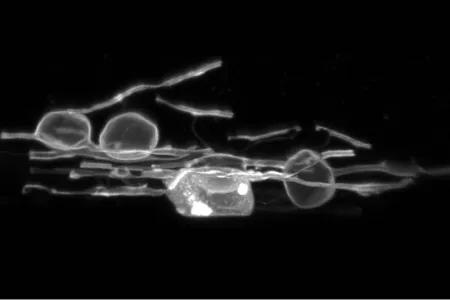

Researchers have uncovered a process by which nerve cells damaged in multiple sclerosis (MS) could potentially repair themselves. Researchers found that myelin – the protective coating surrounding nerves – undergoes an initial swelling phase when damaged, suggesting it may have the ability to heal itself.The findings could offer a significant new opportunity to help slow, stop or even prevent the degeneration of nerve cells in MS and other conditions like Alzheimer's disease. Oligodendrocytes in zebrafish exhibiting myelin swelling Myelin damage In MS, the immune system attacks myelin in the brain and spinal cord and disrupts messages being sent around the body. This impacts how people move, think and feel. There are currently no treatments that can replace damaged or lost myelin.The swelling of myelin has been observed previously, but not investigated in detail. Researchers thought the reaction was linked to the way brain tissue is preserved in the lab.Scientists from the MS Society Edinburgh Centre for MS Research, which is co-lead by Professor Anna Williams of CRM and jointly part of the IRR and the Institute for Neuroscience and Cardiovascular Research (INCR), used advanced technology to observe live zebrafish and tissue from mice and humans who lived with MS to follow what happened to damaged myelin over time. Swelling reaction They found the swelling is a natural process in the body that can be followed by repair of the damaged myelin, suggesting it could be a critical step in the body’s fight to prevent myelin loss.The findings indicate that the nervous system has a powerful – and until now unrecognised – ability to withstand early myelin damage, experts suggest. This offers a potential window of opportunity to intervene before the myelin completely breaks down.The study, funded by the MS Society and Wellcome Trust, was published in the journal Science. These findings suggest that intervening during this early swelling phase could protect myelin before it is lost, offering us to think about potential new treatment routes that would complement current treatments. For decades, scientists have focused on remyelination, the process of rebuilding myelin once it is already lost. This continues to hold promise but now that we have this new avenue of exploration, it could be the start of something else very special. Professor David Lyons Co-lead of the MS Society Edinburgh Centre for MS Research We know that the body has the ability to regenerate new myelin after it’s lost. But this study shows that existing myelin can sometimes self-heal before it’s fully lost, a process we hadn’t focused on before. It doesn’t replace current strategies, but it adds another potential way to protect myelin early on. MS can be debilitating, exhausting and unpredictable and for tens of thousands of people there are still no treatments that work for them. There’s still a lot to learn, but discoveries like this are essential to help people with MS in the future Dr Emma Gray Director of Research at the MS Society Read the study in the journal Science MS Society Edinburgh Centre for MS Research Professor Anna Williams' research Publication date 12 Feb, 2026